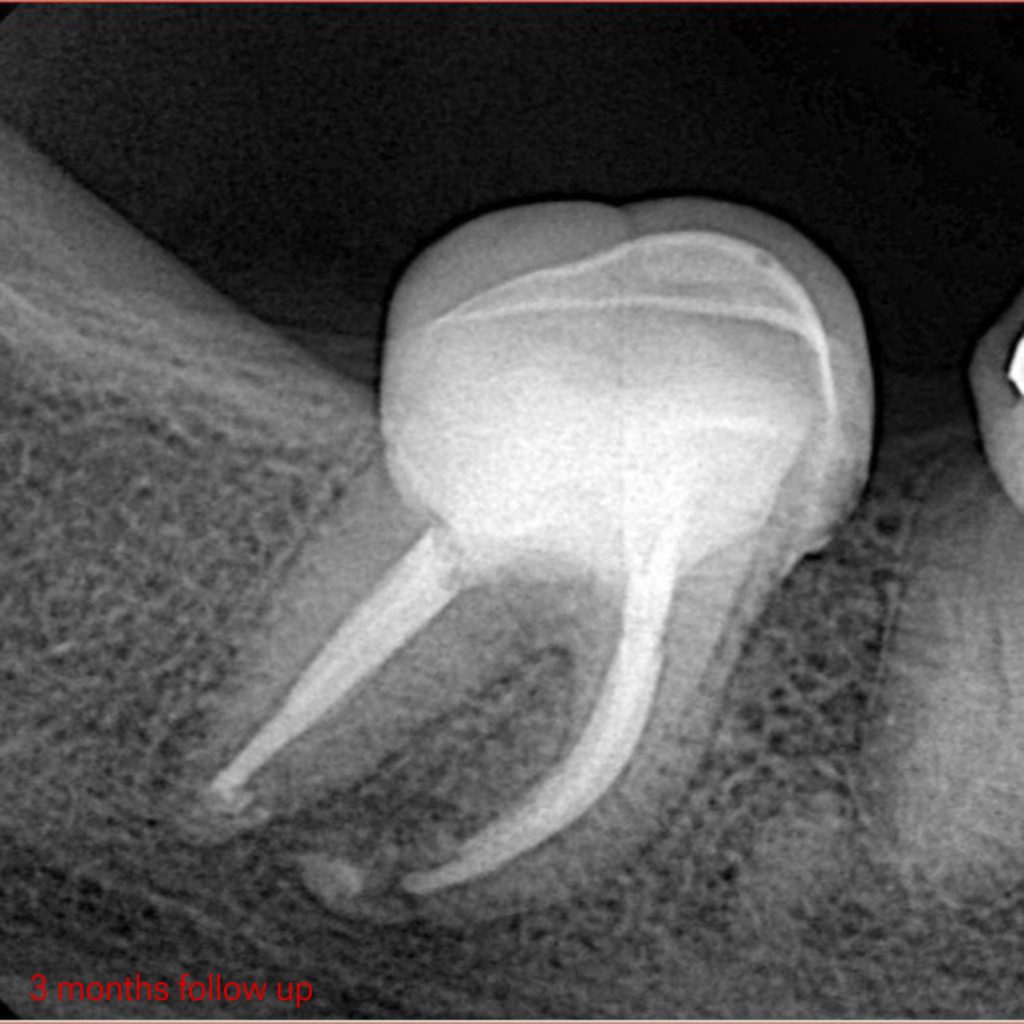

– Follow up after 3 months